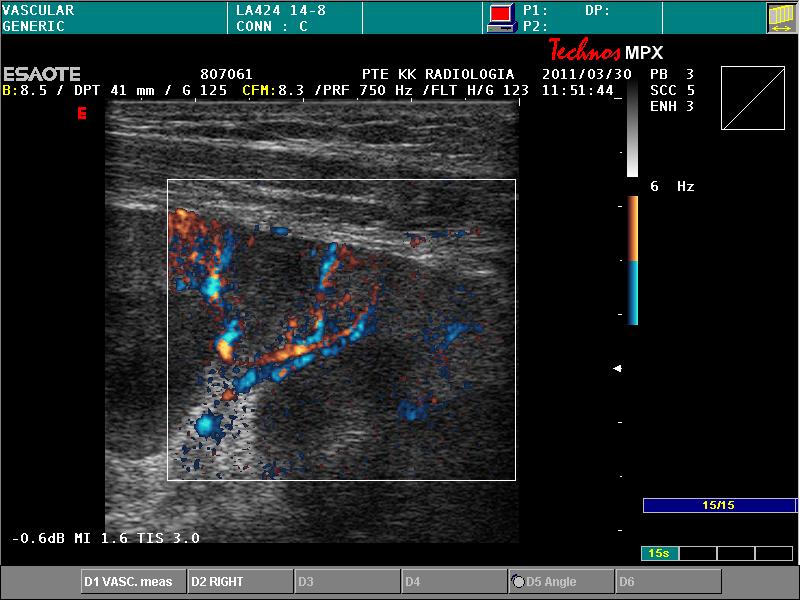

vascularisatiot nem mutat érzékeny paraméterek mellett sem

CEUS: kontraszt-telődés nincsen, de a subcapsularis erekben van áramlás

cortical rim: